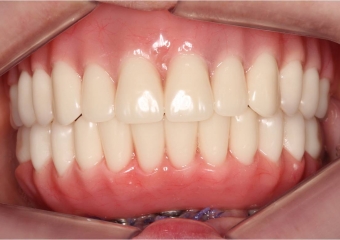

Sorriso após próteses provisórias instaladas - Clínica Cliniface

Sorriso após próteses provisórias instaladas